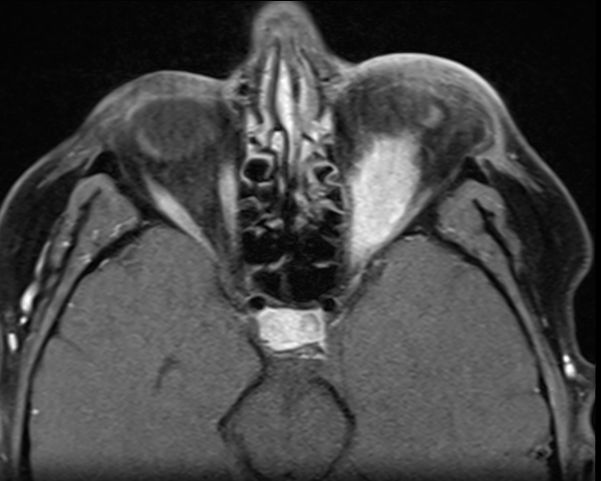

MRT eines retroorbitalen Lymphoms |